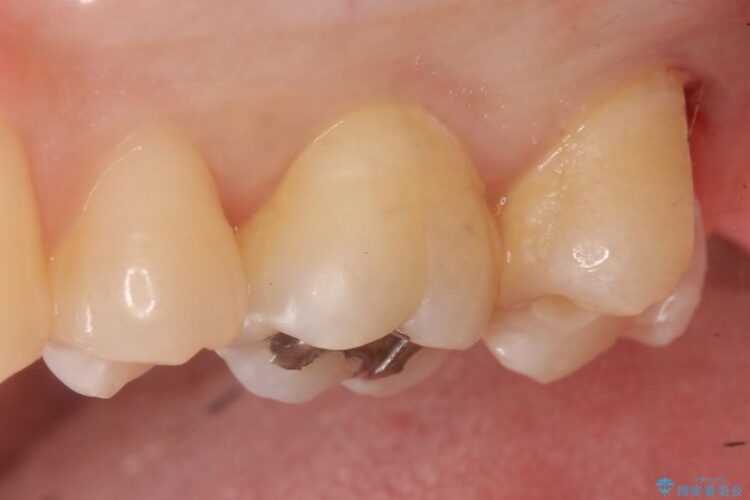

食事中に歯が欠けてしまったとのことで来院されました。

上顎左の一番奥の歯が深い虫歯になって脆くなり、更にその状態に強く噛みしめたわけではない通常の咬合力が加わったことで歯が欠けてしまっていました。